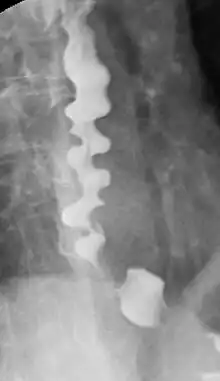

Certain abnormalities on x-ray imaging are commonly observed in DES, such as a "corkscrew esophagus" or "rosary bead esophagus", although these findings are not unique to this condition. Specialized testing called manometry can be performed to evaluate the motor function of the esophagus, which can help identify abnormal patterns of muscle contraction within the esophagus that are suggestive of DES. The treatment of DES consists primarily of medications, such as acid suppressing agents (like proton-pump inhibitors), calcium channel blockers, hyoscine butylbromide, or nitrates. In only extremely rare cases, surgery may be considered. People with DES have higher incidences of gastroesophageal reflux disease (GERD), neuromuscular diseases, and degenerative neurological disorders.

Several radiographic findings are suggestive of DES, such as a "corkscrew esophagus" or "rosary bead esophagus" appearance on barium swallow x-ray, although these findings are not unique to DES.[2]